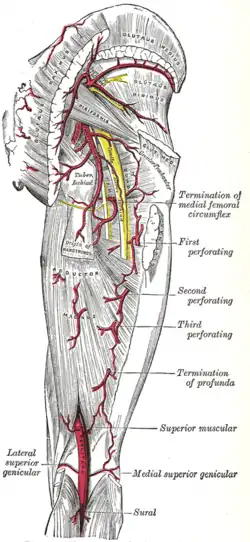

Right femur. Anterior surface. The arteries of the gluteal and posterior femoral regions.

The arteries of the gluteal and posterior femoral regions. Nerves of the right lower extremity Posterior view.